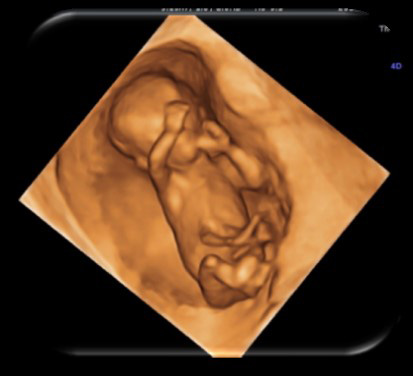

四維超聲 ≠ 排畸篩查

你有沒有在做B超排畸時想看看肚子里的寶寶?據說,能看到小家伙吃手、打哈欠、笑哈哈的樣子。

你有沒有在做四維超聲時,希望能做個排畸篩查?

四維多清楚啊,還是動態的,用它做排畸哪哪都看得清清楚楚的!其實,這些都是錯誤的認識!

超聲檢查以二維超聲為主,四維為輔

模塊專家牛會敏明確地指出:在臨床診斷中,醫院不會把四維超聲作為臨床參考依據的診斷報告,日常超聲檢查還是以二維超聲為主。 普通B超以利用超聲波在充滿羊水的子宮內反射得到的回聲來描繪其中景象,診斷胎兒在母體內發育是否健康,能夠診斷胎兒的畸形。四維圖像需建立在二維超聲切面基礎上,因此是二維超聲技術的主要輔助手段,并不能代替二維超聲

特殊情況使用四維超聲

只有在診斷特殊病例時需要得到立體感強、二維圖像難以提供的標準冠狀切面圖像時,才會短時間的更換四維探頭,使得診斷更為準確。這種特殊情況限于胎兒的顏面部、四肢的結構發育缺陷,因為四維的立體顯示可以大大提高結構缺陷的檢出率。